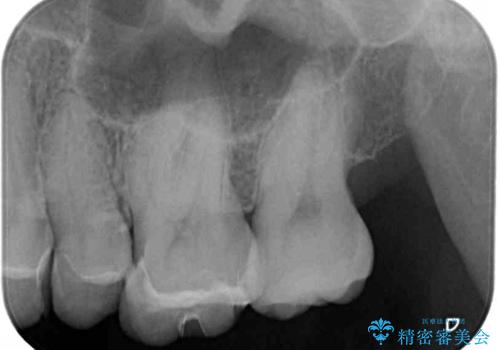

- 奥歯がしみる上に、変色が気になるとのことで来院された患者様です。

診査の結果、不適合なレジンインレーの隙間の接着剤が著しく変色しており、更には頬側の歯肉縁付近に知覚過敏症状が認められました。

健全歯質が多いため、インレーおよびむし歯を除去した上で知覚過敏を緩和させる処置を行うことが望ましいと判断されましたが、知覚過敏の症状が一向に改善されないため、全体をセラミッククラウンで補綴することとしました。